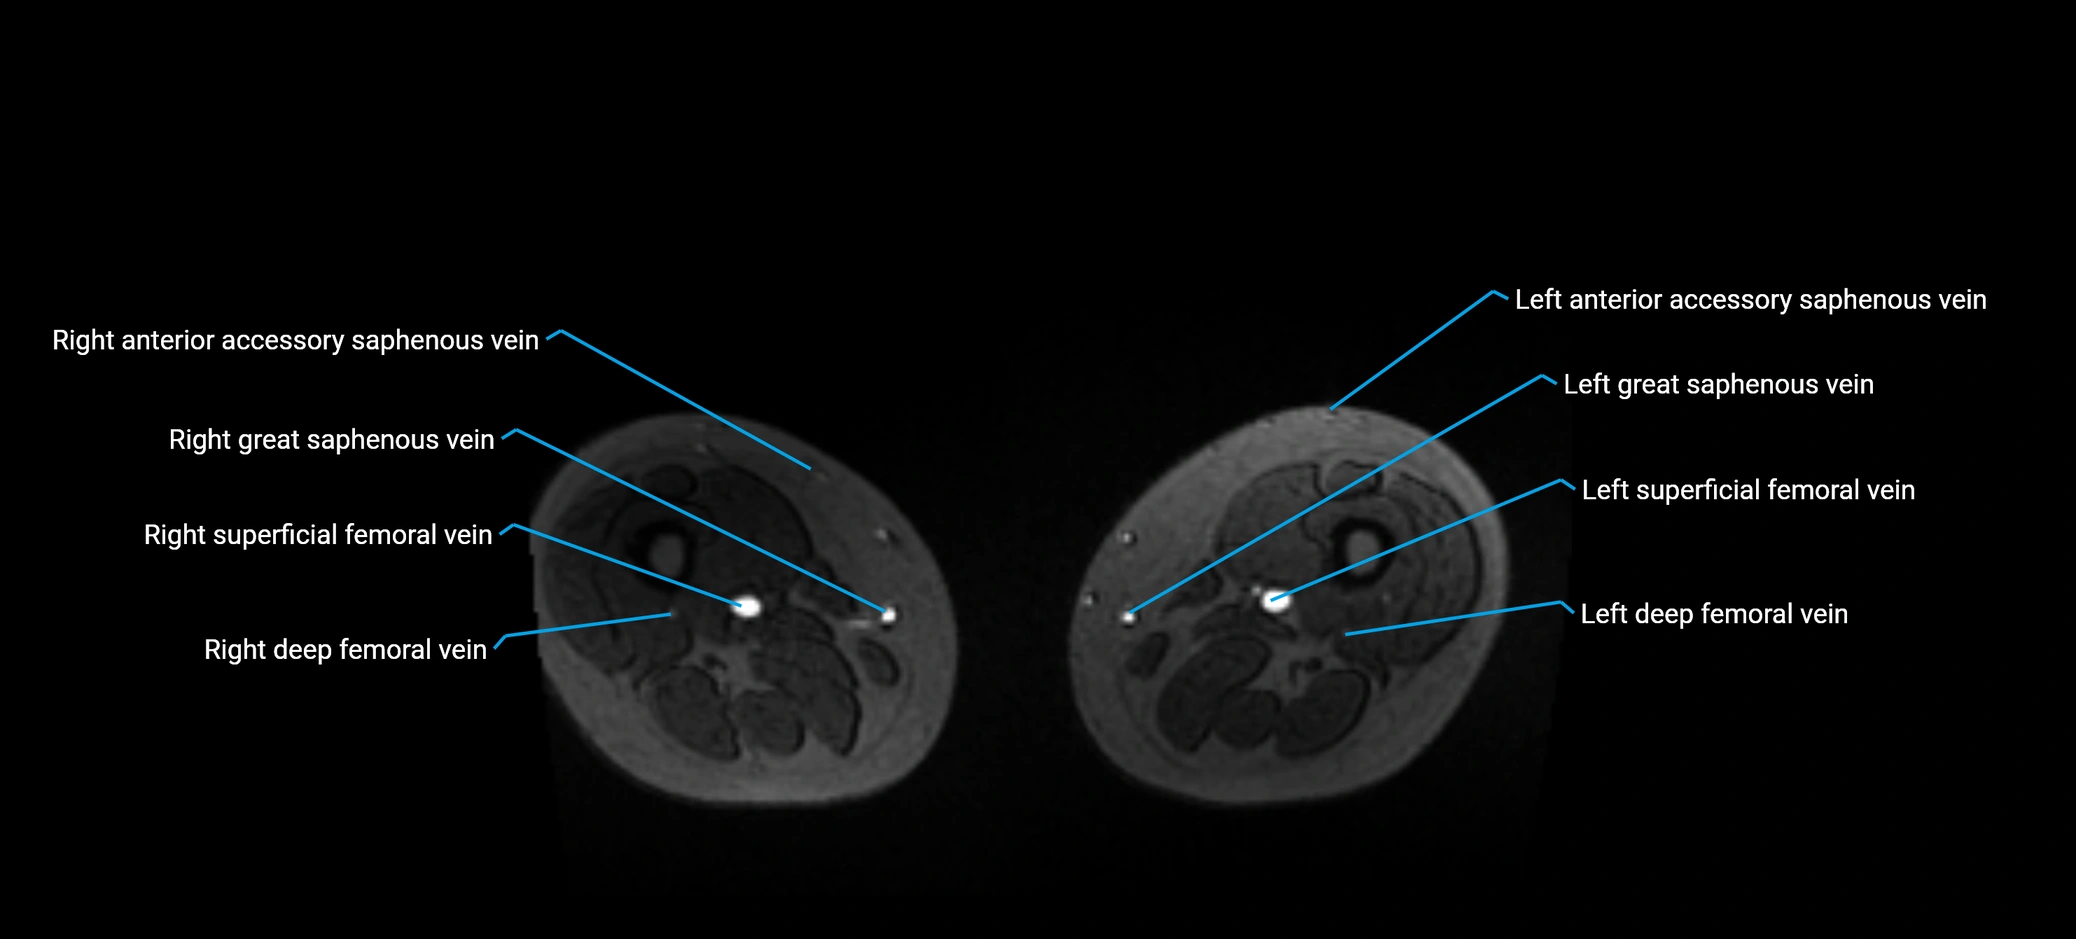

MRI image

image